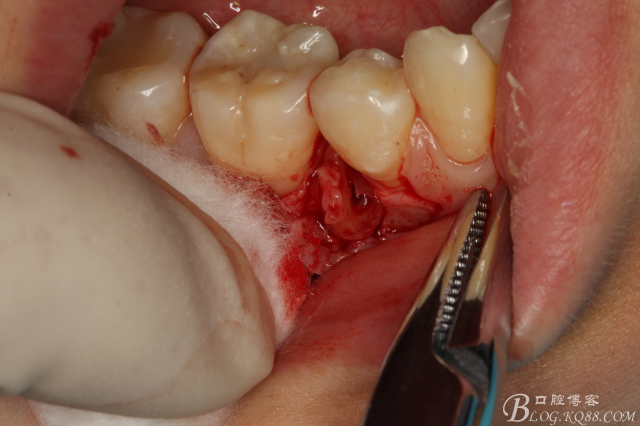

圖15.挺松的45牙根,牙根已脫位至創(chuàng)口邊緣。

圖16.取出45牙根,牙槽窩完整、不變形。

圖17.清理牙槽窩,切口止于膜齦聯(lián)合處,這樣術(shù)后不腫脹。

圖18.放膠質(zhì)銀

圖19.縫合

圖20.拔除的45牙根。